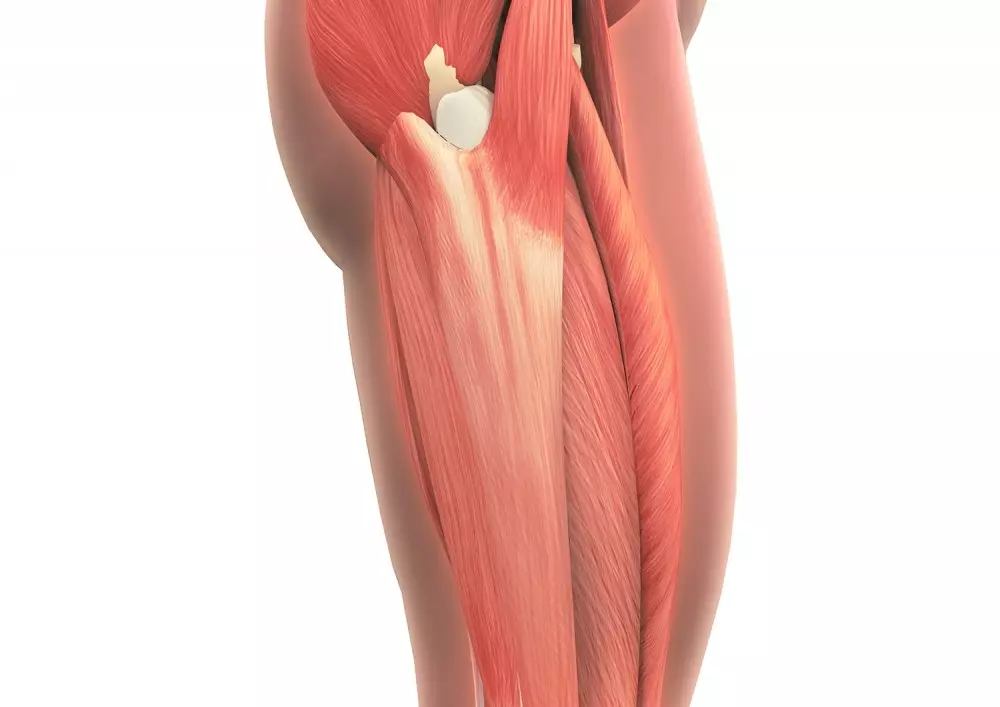

Pasmo biodrowo-piszczelowe

W aktualnym numerze opisujemy również, jak powinna wyglądać terapia pasma biodrowo-piszczelowego. Nie jest to wyraźnie odgraniczona struktura, a raczej zgrubienie powięzi szerokiej uda. Ból w tym obszarze może wynikać z dociskania przez nie tkanki łącznej znajdującej się między pasmem a kością. Pasmo biodrowo-piszczelowe wymaga podjęcia terapii na poziomie tkanek miękkich oraz na poziomie szkieletowym. Opracowanie zawiera wybrane techniki terapeutyczne mające na celu „poprawę funkcji i zmniejszenie napięcia pasma”.